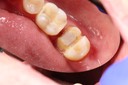

Mark Chun #18 pre-op

Mark Chun #19 caries removal

Mark Chun #18 prep

Mark Chun #18 finish